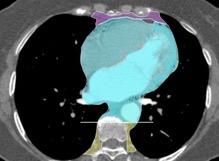

20. ÁREA CARDIACA

21. ÁREA INFRA-AÓRTICA

Aneurisma aórtico

Timo: Timoma, Carcinoma

Causas de afectación

CARDIACO

T. germinales Aneurisma. (Valsalva, VI.)

Quiste pericárdico, del Vent. derecho Hernia de Morgagni

Grasa del ángulo Tumor cardiaco Ganglios diafragmáticos

Quiste timico, Timolipoma Timoma